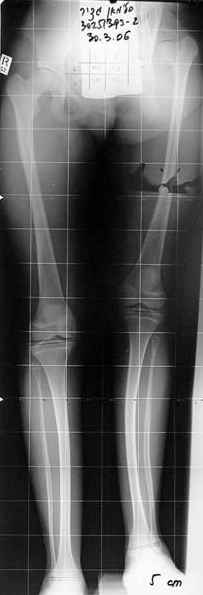

Moghno i tak kak sdelali my: pelvic support + tibial and equinus correction .

Слайд 1

Слайд 2

Слайд 3

Слайд 4

Devushka predstavlennaya na snimke nachala s LLD 9 cm, valgus deformation of the tibia, huge Trendelenburg( vidno na snimke).

Seichas : no LLD ,no Trendelenburg, reasonable hip motion.A samoe glavnoe ei ne predstoit kaghdye 10-15 let delat revision THR.